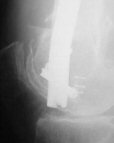

THX, initial images are

1,

2.